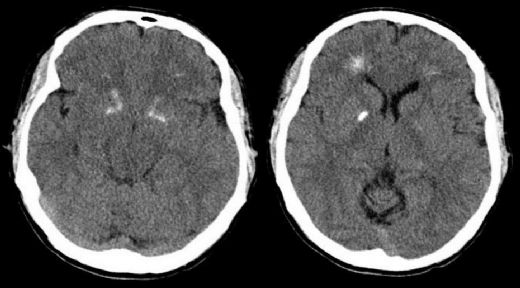

Nedenleri George Sendromu'nun temel nedeni, genetik mutasyonlardır. Çoğu durumda, bu mutasyonlar kromozom 22 üzerinde yer alan bir gende meydana gelir. Genetik mutasyonlar, bireyin gelişiminde önemli rol oynayan proteinlerin işlevini etkileyebilir. Bu sendrom, genellikle kalıtsal bir şekilde geçmez; ancak, bazı durumlarda aile içinde benzer belirtiler gösteren bireyler bulunabilir. Tanısı George Sendromu'nun tanısı, genellikle fiziksel muayene ve bireyin tıbbi geçmişinin incelenmesi ile konulur. Belirtilerin yanı sıra, genetik testler de tanının kesinleşmesine yardımcı olabilir. Genetik danışmanlık, sendromun aile içindeki olası geçişi hakkında bilgi sağlayabilir. Tedavi Yöntemleri George Sendromu için spesifik bir tedavi yöntemi bulunmamaktadır. Ancak, belirtilerin yönetimi ve bireyin yaşam kalitesinin artırılması amacıyla çeşitli terapi ve tedavi yöntemleri uygulanabilir. Bu yöntemler arasında şunlar yer alır: